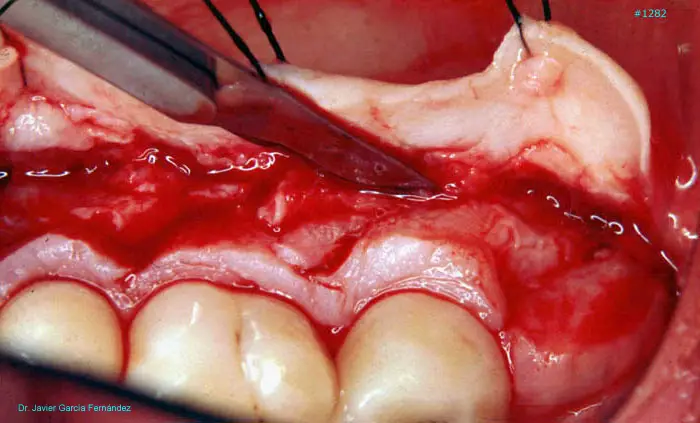

Atlas of Surgical Techniques in Periodontics. Chapter III. Atlas de Técnicas Quirúrgicas en Periodoncia